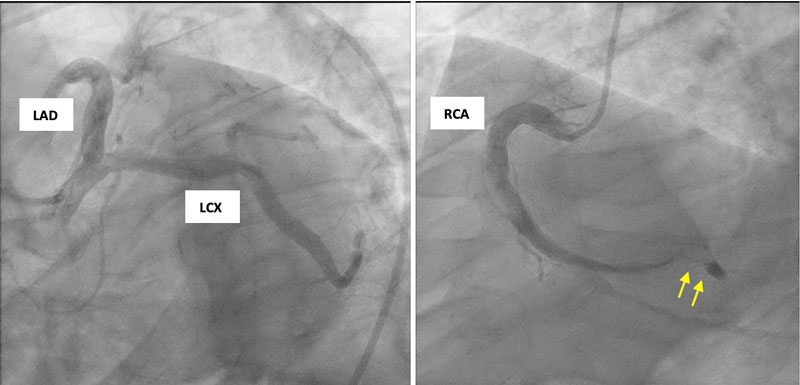

Code STEMI was activated. The patient received 324 mg of aspirin, 80 mg of atorvastatin, one nitroglycerin tablet, and an intravenous heparin drip prior to being transferred for emergent cardiac catheterization. Coronary angiography demonstrated diffuse, severe coronary artery ectasia (Figure 2) with complete (100%) thrombotic occlusion of the distal RCA and a large thrombus burden at the mid-RCA segment (Figure 2). PCI was performed with the placement of a drug-eluting stent in the distal RCA, resulting in the restoration of TIMI III flow to the right posterior descending artery. However, a residual thrombus remained in the mid-to-distal RCA, and occlusion of the right posterior ventricular branch persisted (Figure 3).

Figure 3

Figure 3 Residual large thrombus in the mid-right coronary artery (RCA) segment following intervention (yellow arrow).